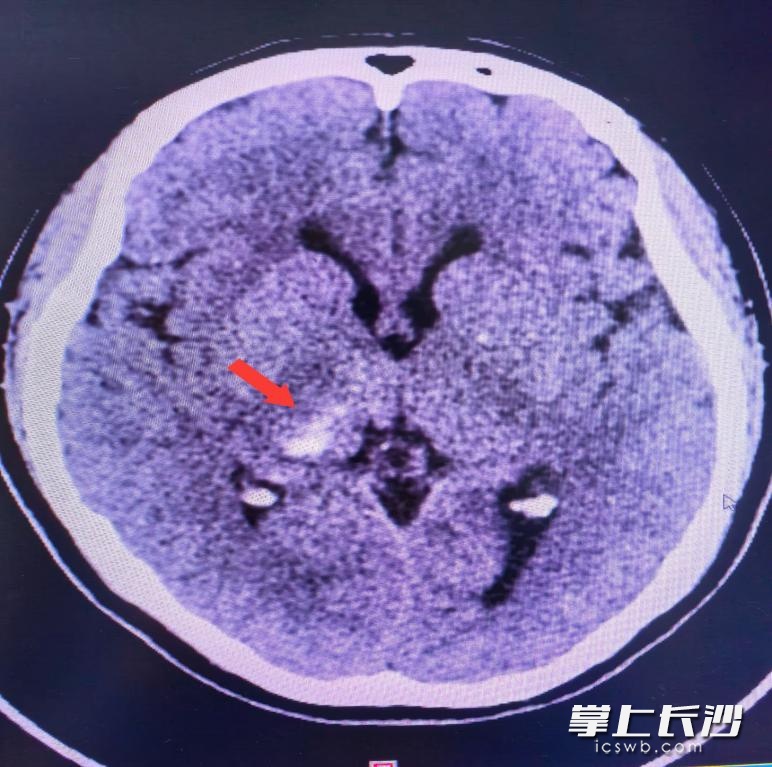

接诊的是该院脑血管神经外科主任医师刘坤,经过详细检查,他发现梁女士出现突发脑出血。万幸的是梁女士颅内出血量不多,住院期间,经精细治疗,排除其他高危因素,加上脑心健康管理师全程管理及宣教,经复查显示颅内出血基本吸收,梁女士痊愈顺利出院。

梁女士CT检查结果显示颅内出血。通讯员 供图